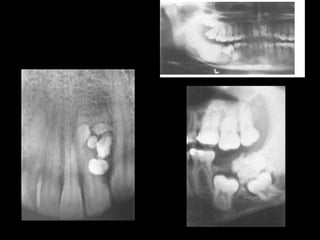

TYPES: complex and compound odontome.

1.COMPLEX: most common in posterior mouth.

Amorphous conglomeration of dental tissues

consisting of enamel,dentin and cementum. Radiograph

shows gives a radiopaque mutilobular appearance.

2.COMPOUND: common in anterior jaw.contains

numerous denticles or tooth like fragments (each

containing enamel with dentin and pulp)

3. Radiographical resembles a bag of teeth